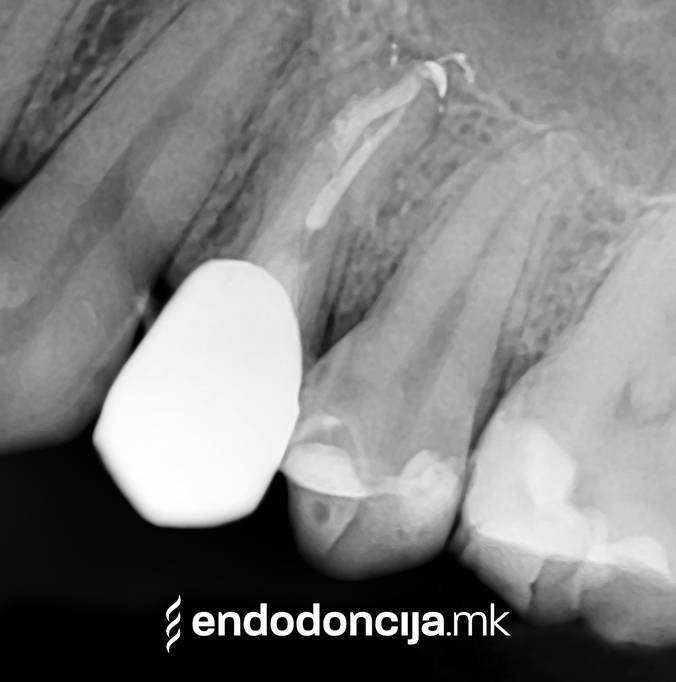

Κατά τη διάρκεια προηγούμενων θεραπειών, το δόντι μπορεί όχι μόνο να έχει αποδυναμωθεί από τη μηχανική επεξεργασία του ριζικού σωλήνα αλλά και από τη στερέωση και την αγκύρωση ενός ρίζα. Όταν αναθεωρείται η επεξεργασία ενός ριζικού καναλιού, αυτοί οι πείροι πρέπει να αφαιρούνται όσο το δυνατόν πιο προσεκτικά για να διατηρούν σημαντική ουσία των δοντιών.

Σε περίπτωση ανανέωσης της θεραπείας του ριζικού καναλιού (αναθεώρηση) παλιά γεμίσματα ρίζας που δεν ήταν επιτυχημένα και ως εκ τούτου ήταν η αιτία φλεγμονών και πόνου, μπορούν να αφαιρεθούν και να ανανεωθούν εξειδικευμένα. Αυτή η θεραπεία εξαλείφει τις φλεγμονές στην περιοχή της ρίζας και καθίσταται δυνατή η πλήρης ανάρρωση.